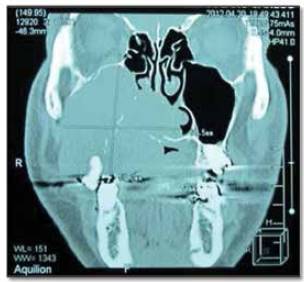

Se realiza un estudio imagenológico por medio de una tomografía computadorizada. Los resultados confirman una lesión de gran tamaño de alrededor de 6,1 x 5,8 centímetros de extensión. El corte coronal muestra comprometida parte del hueso palatino y maxilar, y se observa la completa obliteración del seno maxilar derecho y adelgazamiento de sus tablas corticales (compárese con el seno maxilar izquierdo). La lesión se extiende hasta el piso de la órbita ocular derecha, también invade la región nasal, y afecta los cornetes medio e inferior derechos y supera la línea media nasal (figura 3). El corte axial hace evidente la expansión, adelgazamiento y perforación de la tabla cortical vestibular del cuadrante derecho, así como la expansión de la lesión hacia la línea media del paciente, lo que compromete y obstruye de forma parcial la vía aérea superior (figura 4).